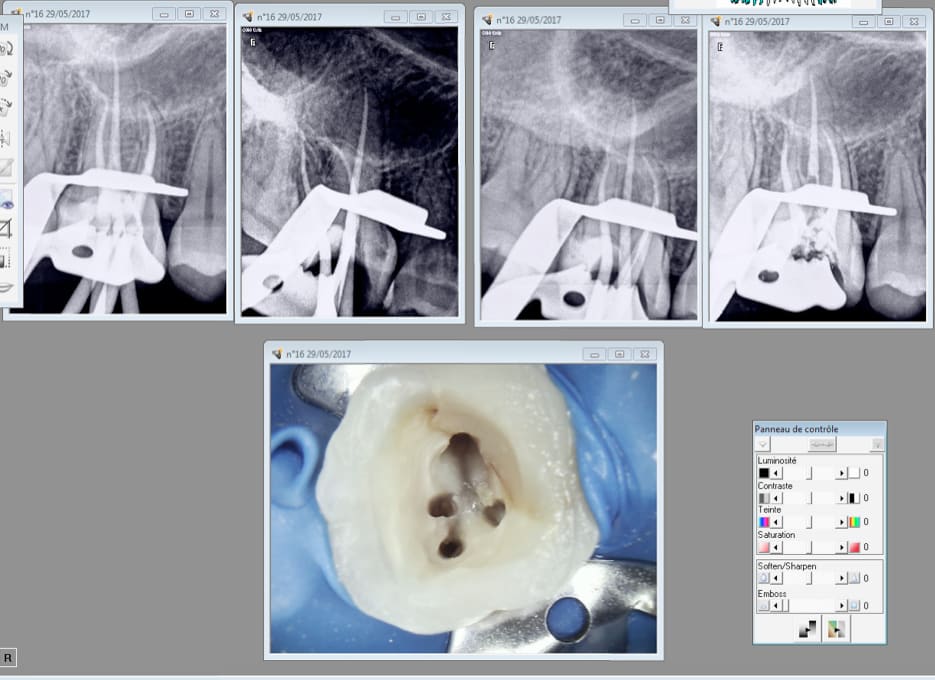

Capture d écran 2017 07 03 21.01 - Eugenol

Et ca ca vaut quoi ?

Capture d écran 2017 07 03 21.08 - Eugenol